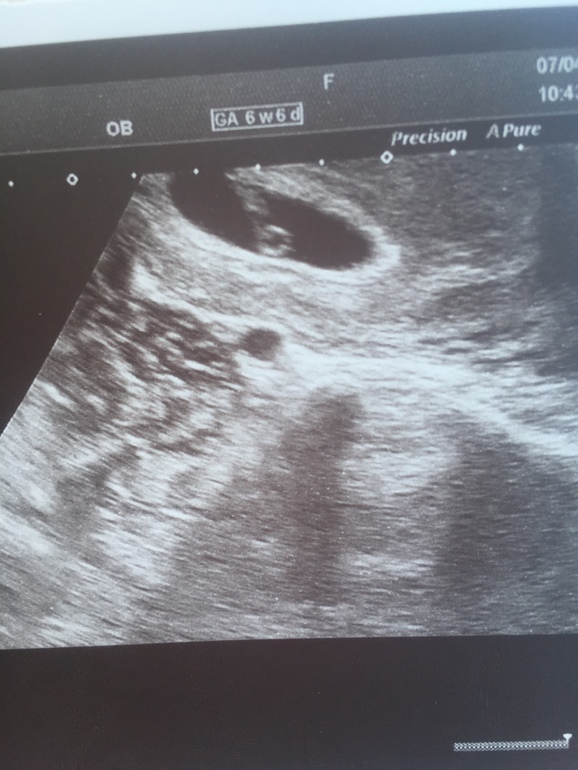

Анна в Зачатие 8 лет Один или два Фолликулометрия Девочки может тут быть два плода просто непонятно Посмотрите еще 20 записей на эту тему Отменить Ответить Ведана мой инстаграм vedana tarolog один 23.04.2018 Ответить Марина Одна ляличка,поздравляю Вас и здоровья Вам крепкого😊🌺🌺🌺 23.04.2018 Ответить Дарья Один 23.04.2018 Ответить Нина Я вижу малыша сверху и внизу кругленький желточный мешок) 23.04.2018 Ответить Стану мамой Я в узи не сильна, но тут вижу эмбриончик сверху и желточный мешочек снизу. ☺️ 23.04.2018 Ответить Аня По мне так один. 23.04.2018 Ответить Ксюня Тут Один,ну или одна))) 23.04.2018 Ответить На УЗИ в яичиках все тихо Радовалаться или плакать?? Чаты Беременных Выберите чат: Январята-2026 Февралята-2026 Мартята-2026 Апрелята-2026 Майчата-2026 Июнята-2026 Июлята-2026 Августята-2026